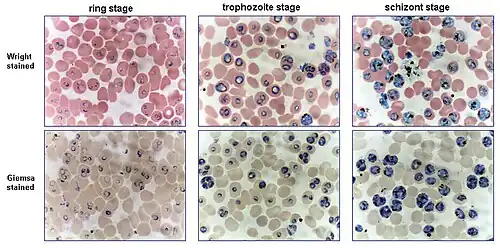

Routine analysis of blood in medical laboratories is usually performed on blood films stained with Romanowsky stains such as Wright's stain, Giemsa stain, or Diff-Quik. Wright-Giemsa combination stain is also a popular choice. These stains allow for the detection of white blood cell, red blood cell, and platelet abnormalities. Hematopathologists often use other specialized stains to aid in the differential diagnosis of blood disorders.

The preferred and most reliable diagnosis of malaria is microscopic examination of blood smears, because each of the four major parasite species has distinguishing characteristics. Two sorts of blood smear are traditionally used.[9]

- Thin smears are similar to usual blood films and allow species identification, because the parasite's appearance is best preserved in this preparation.

- Thick smears allow the microscopist to screen a larger volume of blood and are about eleven times more sensitive than the thin film, so picking up low levels of infection is easier on the thick film, but the appearance of the parasite is much more distorted and therefore distinguishing between the different species can be much more difficult.[10][9]

From the thick smear, an experienced microscopist can detect all parasites they encounter. Microscopic diagnosis can be difficult because the early trophozoites ("ring form") of all four species look identical and it is never possible to diagnose species on the basis of a single ring form; species identification is always based on several trophozoites.